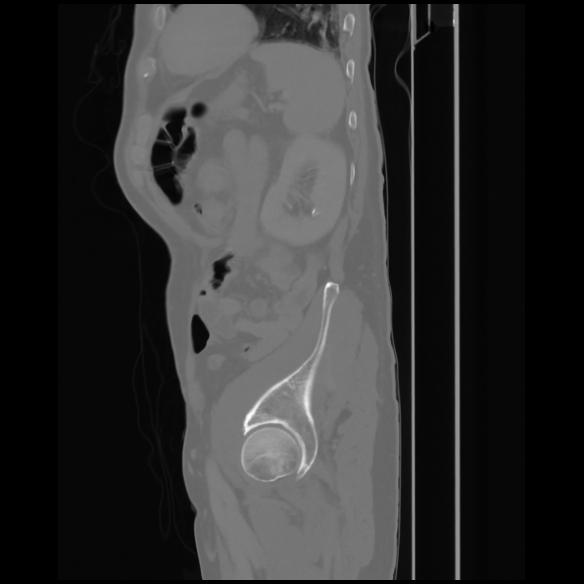

7 CUERPO,CE,Sagittal,3.000,CUERPO,Sagittal,